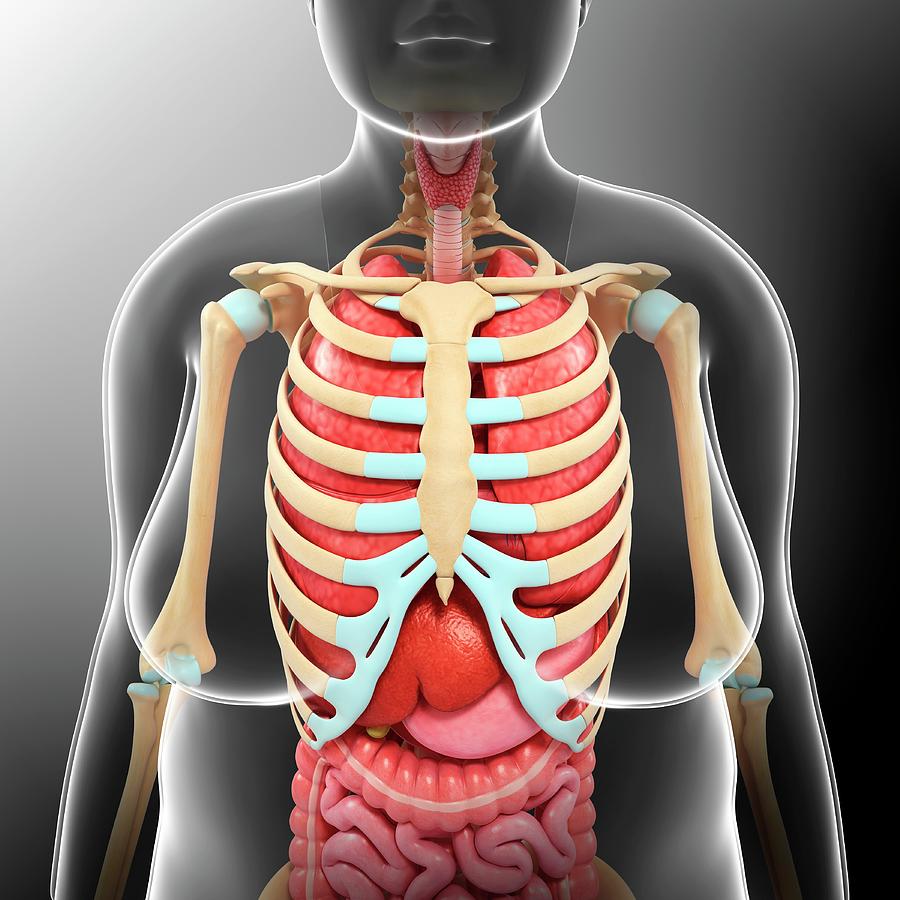

Torso Anatomy : Diagram Woman Of Upper Torso Diagram Full Version Hd Quality Torso Diagram  How to Draw the Female Torso, an in-Depth Guide â GVAAT'S WORKSHOP

Female Upper Torso Anatomy - Human Female Torso Anatomy 3d model - CGStudio : Anatomy study of  Torso Anatomy Plate French Vintage Original Print 1920's - Etsy

Upper Torso Anatomy Drawing : Human Rib Cage Drawing at GetDrawings | Free download : That's a  Back Muscles Drawing Reference Female : Muscle Drawing at GetDrawings | Free download / Human

PPT - Atlas A General Orientation to Human Anatomy PowerPoint Presentation - ID:774094  Torso Anatomy Female - 42cm Tall Human Anatomical Female Torso Model | Torso / You really